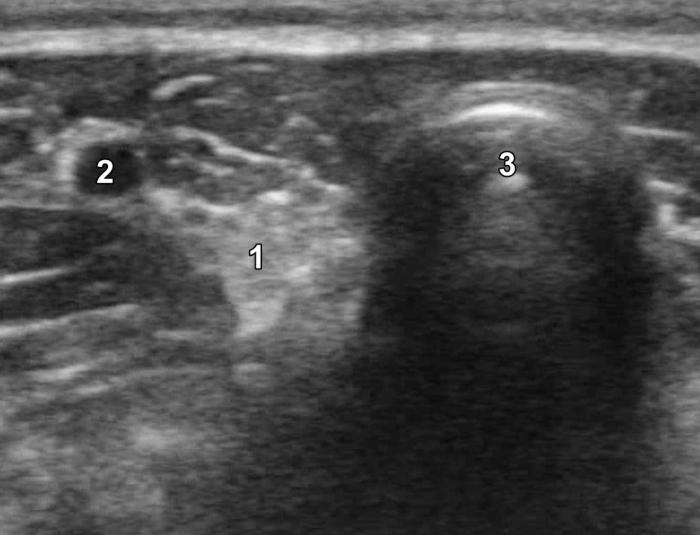

La glándula tiroides en perros y gatos está constituida por dos lóbulos situados a ambos lados de la tráquea cervical, con disposición longitudinal y una forma fusiforme o alargada que se extiende desde el cartílago cricoides hasta la entrada torácica superior2. En condiciones normales, cada lóbulo presenta contornos bien definidos, cápsula hiperecogénica delgada y parénquima homogéneo, con una ecogenicidad generalmente igual o ligeramente superior al músculo esternohioideo adyacente3,8. En la imagen transversal, los lóbulos suelen adoptar una configuración oval o ligeramente triangular (Figura 1); en longitudinal, se observa una forma alargada con extremos redondeados y orientación paralela a los vasos carotídeos y la tráquea1 (Figura 2).

La localización anatómica superficial de la glándula, junto con su estructura relativamente uniforme, facilita su identificación mediante ultrasonografía de alta resolución. Entre los reparos anatómicos más importantes para su localización se encuentran las arterias carótidas comunes (laterales), la tráquea (medial) y los músculos esternotiroideos (ventrales), mientras que el esófago puede constituir una referencia dorsal del lóbulo izquierdo15 (Figuras 3 y 4).

Las glándulas paratiroides, encargadas de la regulación del metabolismo del calcio, pueden ser evaluadas mediante ecografía, aunque su identificación depende de la experiencia del ecografista, la calidad del equipo y la presencia o no de patología subyacente3. En condiciones normales, estas glándulas son pequeñas (menores de 3-4 mm), isoecogénicas o ligeramente hipoecogénicas respecto al tejido tiroideo (Figura 15A-B; ver Figura 2), y se ubican en las proximidades del polo craneal y caudal de cada lóbulo tiroideo1.